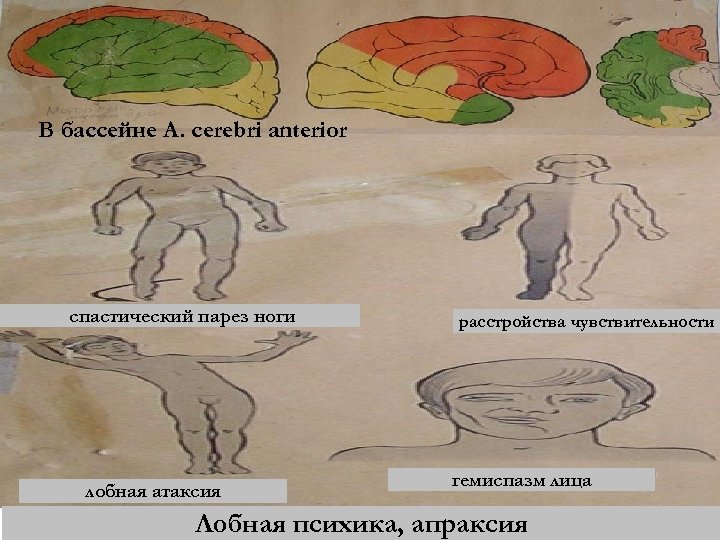

В бассейне А. cerebri anterior спастический парез ноги лобная атаксия расстройства чувствительности гемиспазм лица Лобная психика, апраксия

В бассейне А. cerebri anterior спастический парез ноги лобная атаксия расстройства чувствительности гемиспазм лица Лобная психика, апраксия